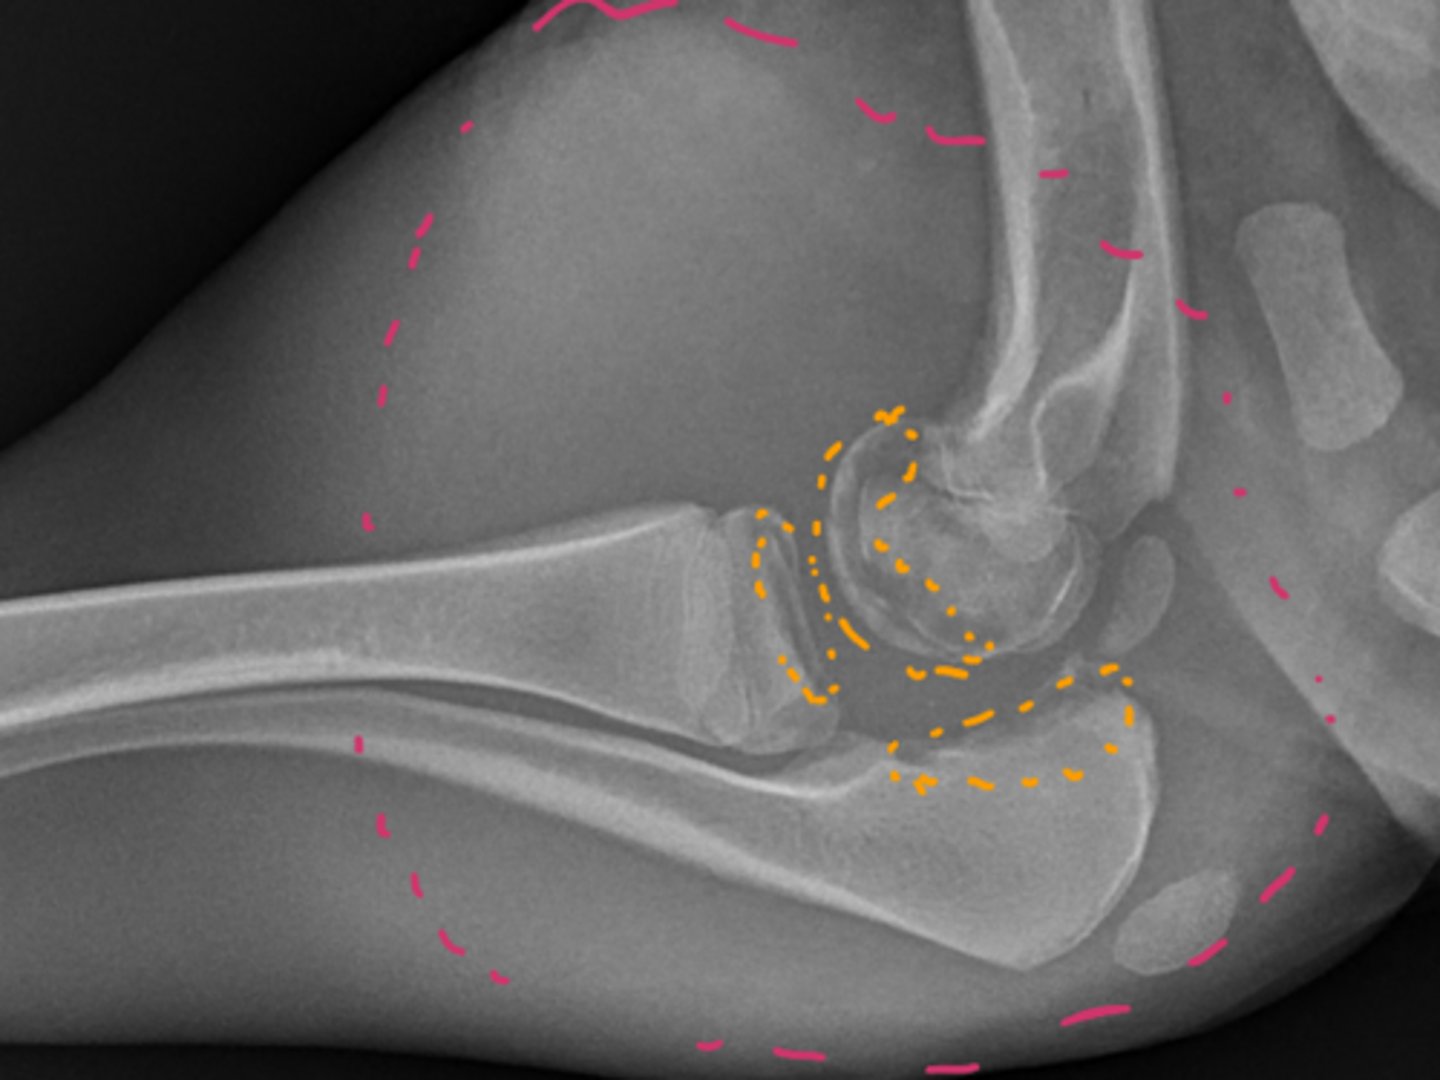

Identify the joint changes?

Monoarthrosis - Osteoarthritis - smooth regular bone less swelling